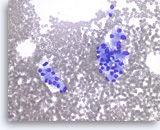

Non-Hodgkin B-cell lymphoma,

Pancreas FNA, Direct Smear.

The aspirates show dispersed single intermediate to large atypical lymphocytes.

20X

Non-Hodgkin B-cell lymphoma,

Pancreas FNA, Direct Smear.

The aspirates show dispersed single intermediate to large atypical lymphocytes.

20X

Non-Hodgkin B-cell lymphoma,

Pancreas FNA, Direct Smear.

At a higher magnification, the atypical lymphocytes show variations in size and shape. Scattered lymphoglandular bodies are seen in the background.

40X

Non-Hodgkin B-cell lymphoma,

Pancreas FNA, Direct Smear.

At a higher magnification, the atypical lymphocytes show variations in size and shape. Scattered lymphoglandular bodies are seen in the background.

40X